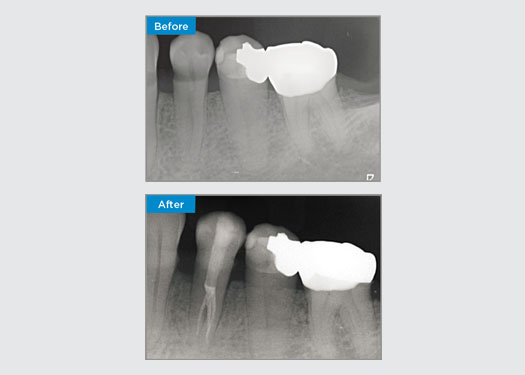

Questo paziente presentava un restauro distale-occlusale rotto sul dente 46. La ricostruzione esistente del dente si estendeva molto in profondità e vicino alla camera pulpare. Date le grandi dimensioni del restauro, era altamente probabile che se semplicemente sostituissimo il restauro con un altro restauro diretto, il risultato sarebbe lo stesso, con la rottura del restauro sotto i carichi occlusali a cui sono sottoposti il dente e il restauro. Quindi, è stata raccomandata un'opzione indiretta per il dente. Poiché il terzo mesiale del dente non è stato ampiamente influenzato dalla sostanziale struttura dentale solida rimanente, potremmo preservarlo ed essere minimamente invasivi, ripristinando il dente con un restauro indiretto utilizzando il sistema CEREC

Dott. Sahil Soni, Queensland, Australia